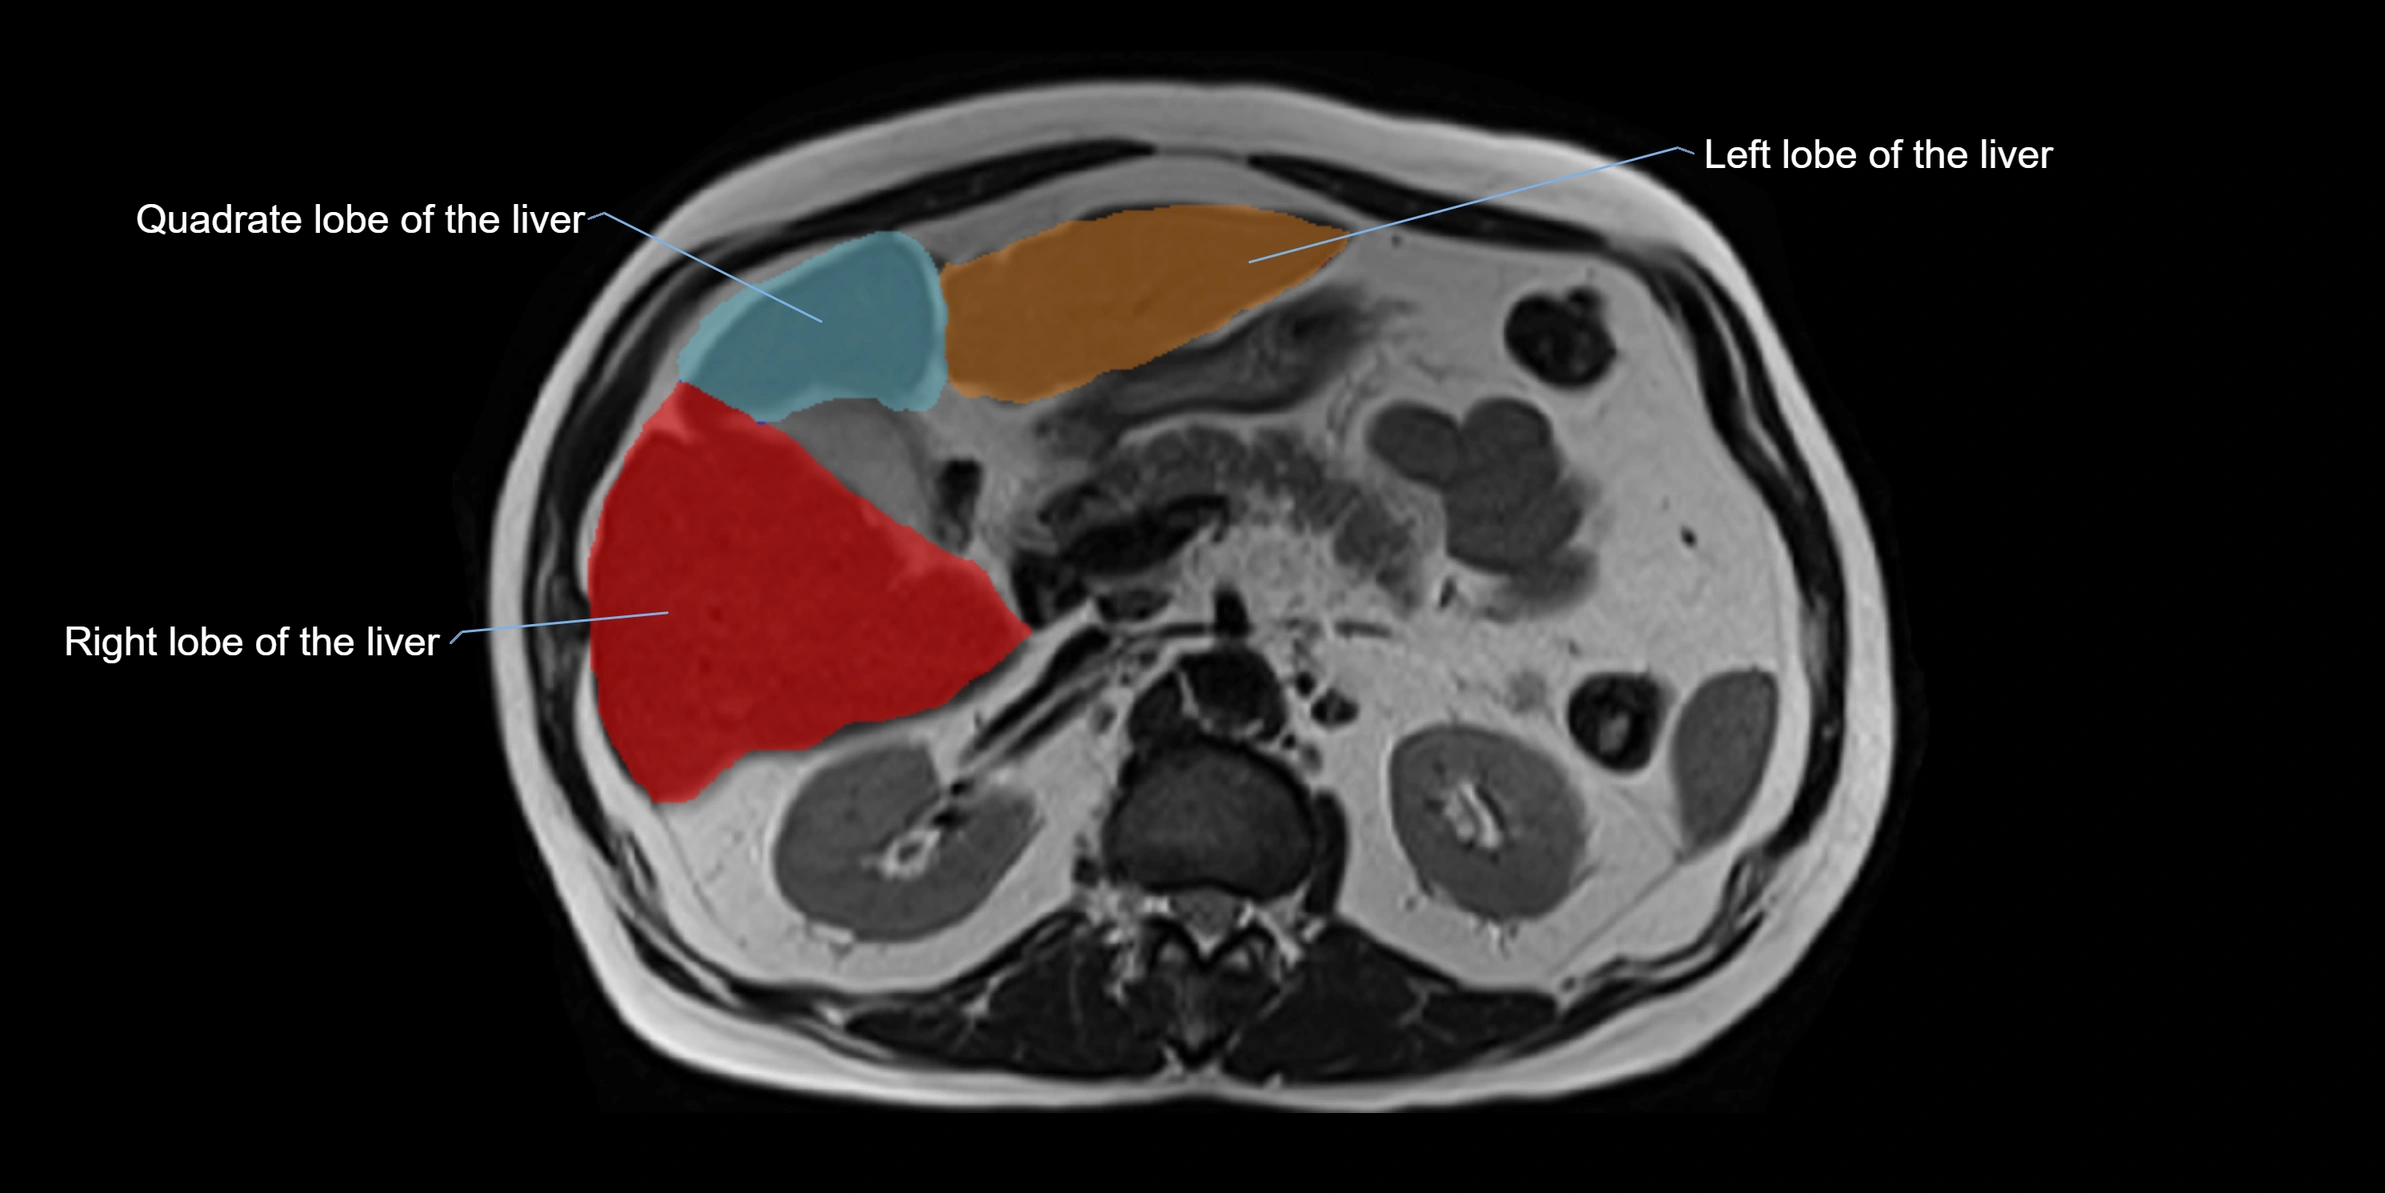

MRI image

image